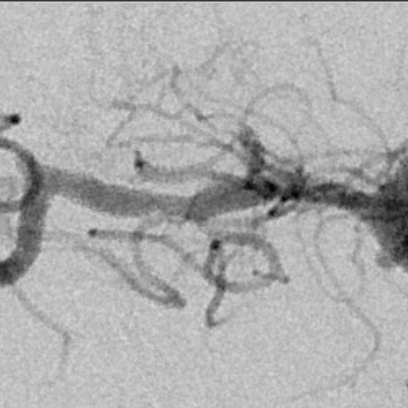

右侧MCA长节段血管变细狭长

长节段MCA血管狭长变细,尤以近端为重

乍一看血管似乎还可以

放大后仔细观看,近端有局限性血管变细,并见双腔征

另外时相远端也隐约局限性变细

观察,血管形态还可以,血流顺流

继续观察